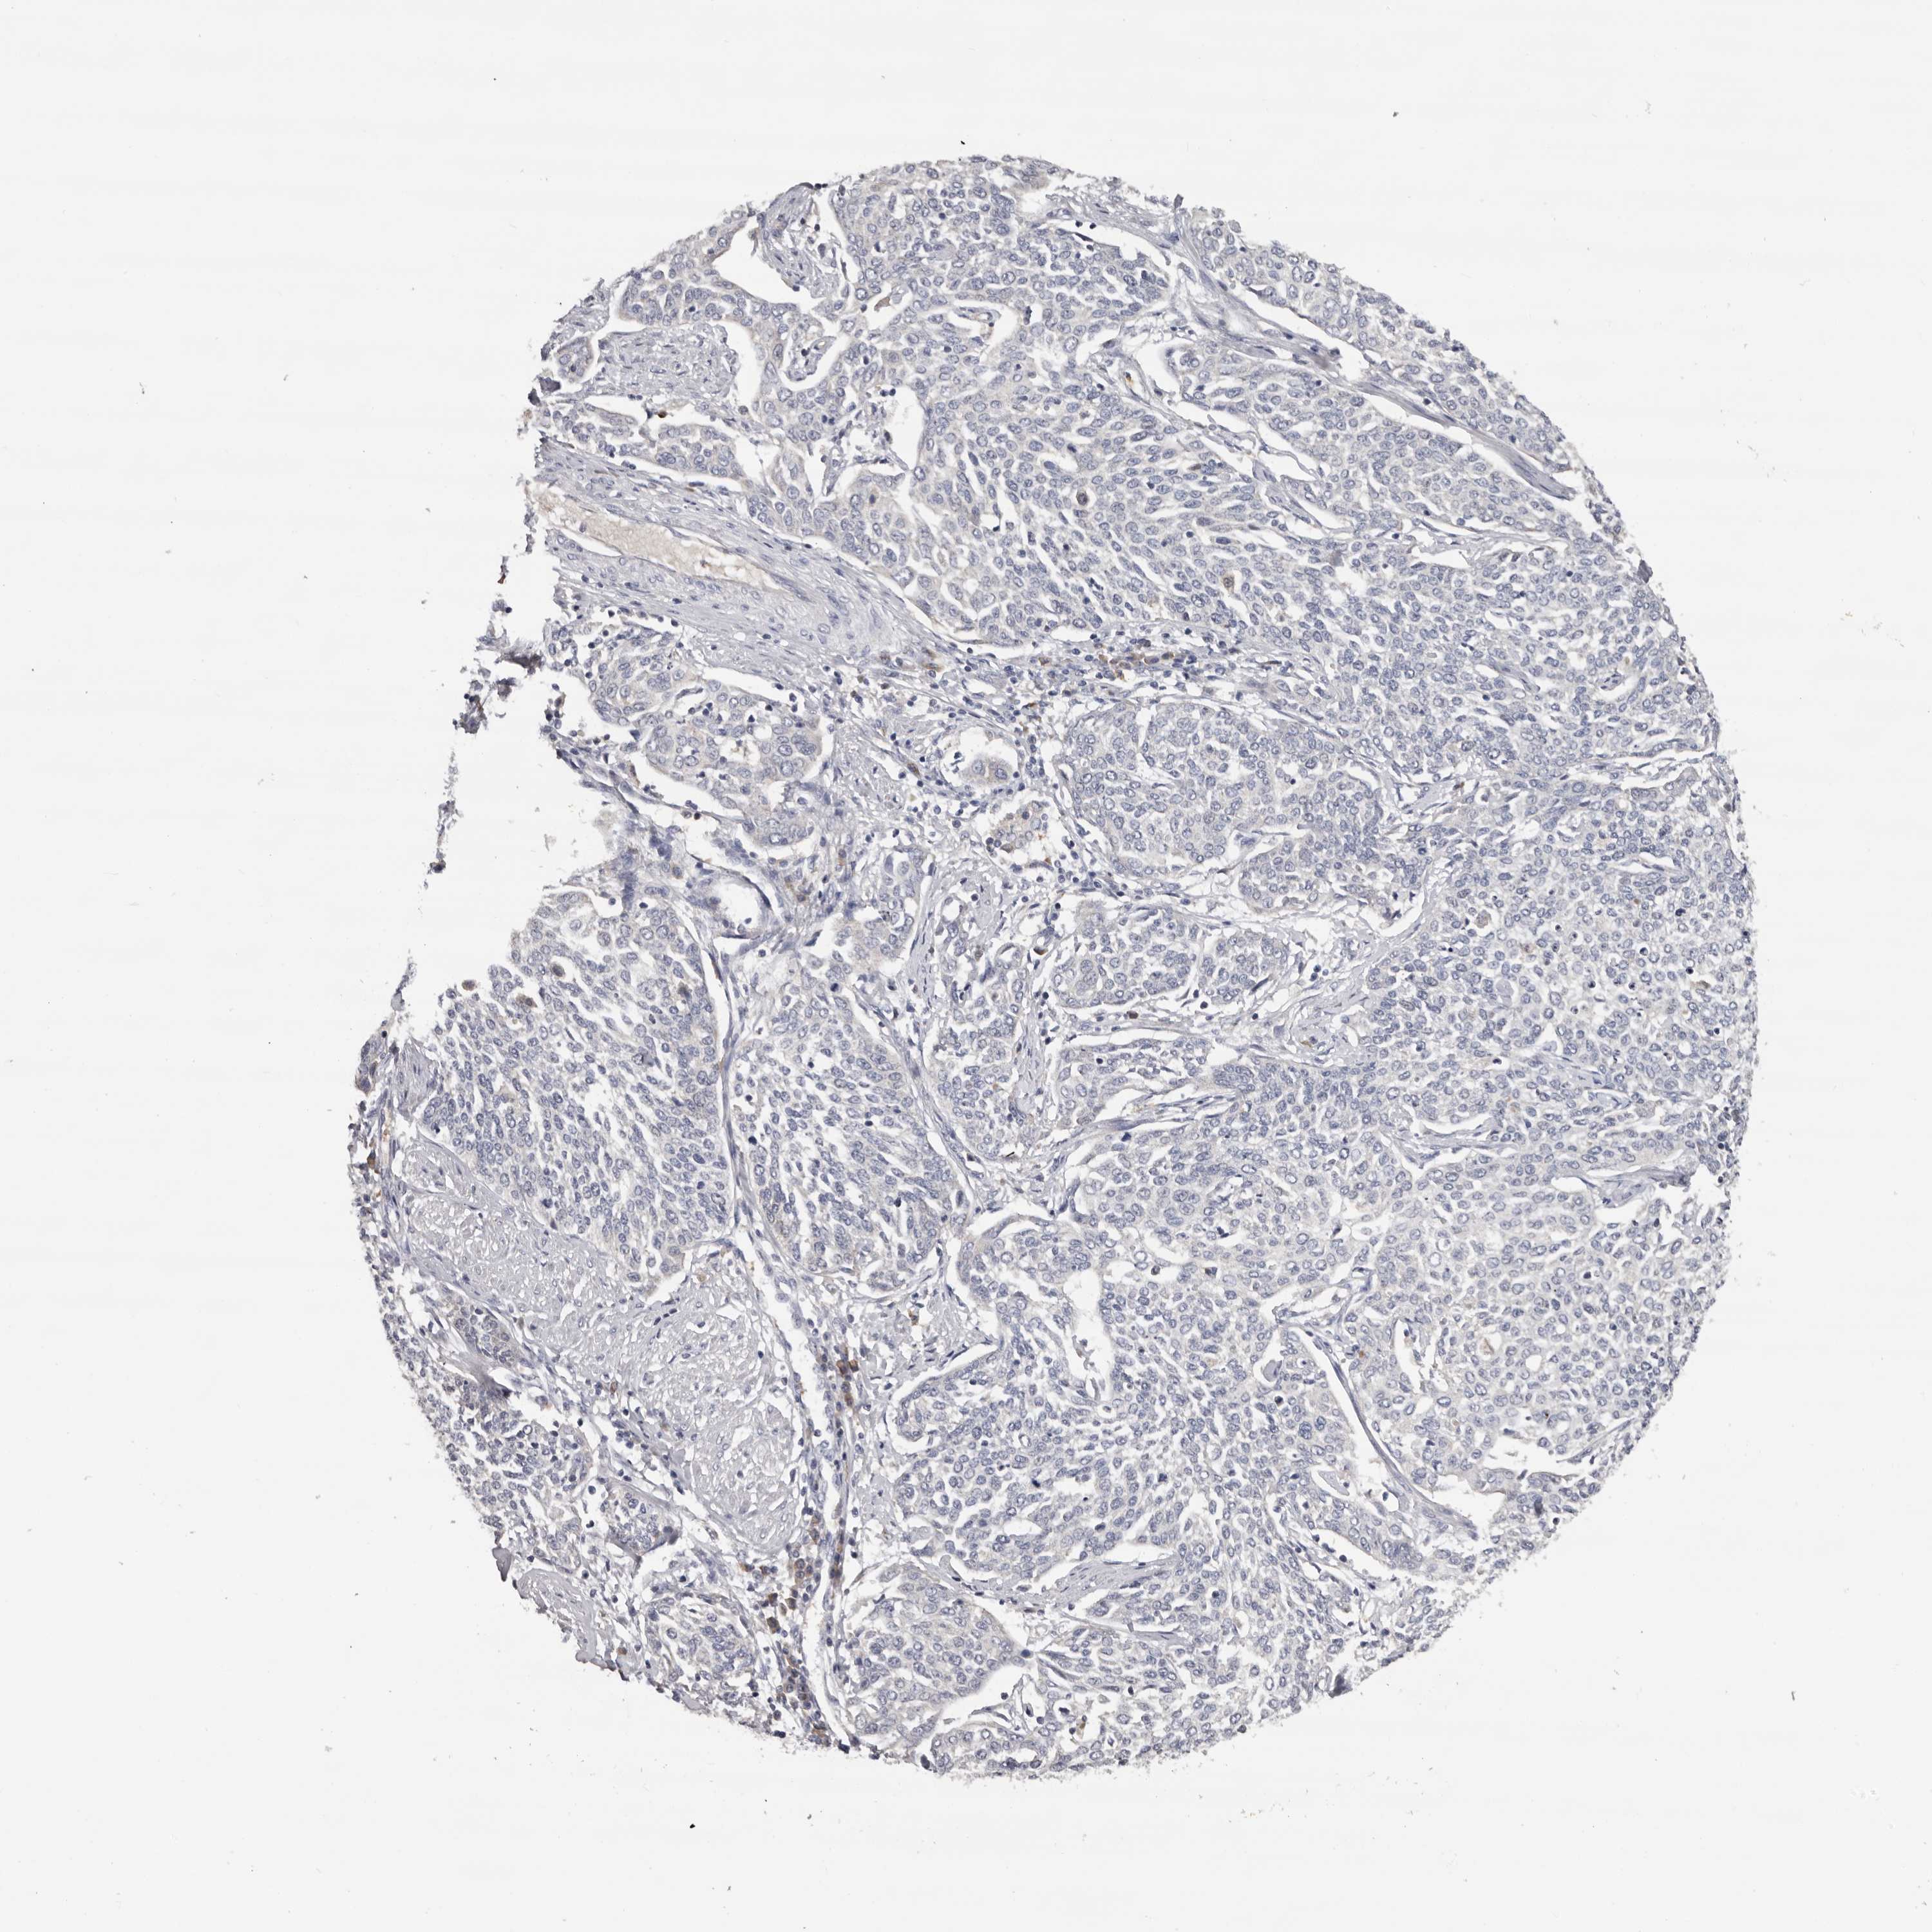

CERVICAL CANCER - Protein expressioni

A mouse-over function shows sample information and annotation data. Click on an image to view it in a full screen mode. Samples can be filtered based on level of antibody staining by selecting one or several of the following categories: high, medium, low and not detected. The assay and annotation is described here.

Note that samples used for immunohistochemistry by the Human Protein Atlas do not correspond to samples in the TCGA dataset.

Antibody stainingi

Antibody staining in the annotated cell types in the current human tissue is reported as not detected, low, medium, or high, based on conventional immunohistochemistry profiling in selected tissues. This score is based on the combination of the staining intensity and fraction of stained cells.

Each image is clickable and will lead to virtual microscopy that enables deeper exploration of all samples and also displays staining intensity scores, fraction scores and subcellular localization as well as patient and tissue information for each sample.

Antibody HPA023103

Adenocarcinoma, NOS